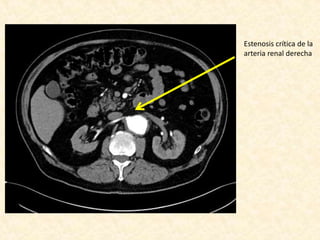

• Estenosis crítica de la arteria renal derecha

Estenosis crítica de la

arteria renal derecha

Informe • Leve dilataciónde arco aórtico • La aorta descendente se presenta elongada, tortuosa y presenta un gran aneurisma que compromete gran parte de su extensión, el cual se inicia aproximadamente 6 cm del origen de la subclavia izquierda, se extiende por aproximadamente 15 cm, y alcanza un diámetro máximo de 10 cm, con trombosis aproximadamente del 60% de la luz. • La aorta abdominal es tortuosa, con ateroma severo de predominio de placas no calcificadas, sin aneurismas. • Estenosis crítica de la arteria renal derecha • Riñones levementes asimétricos por menor tamaño del derecho